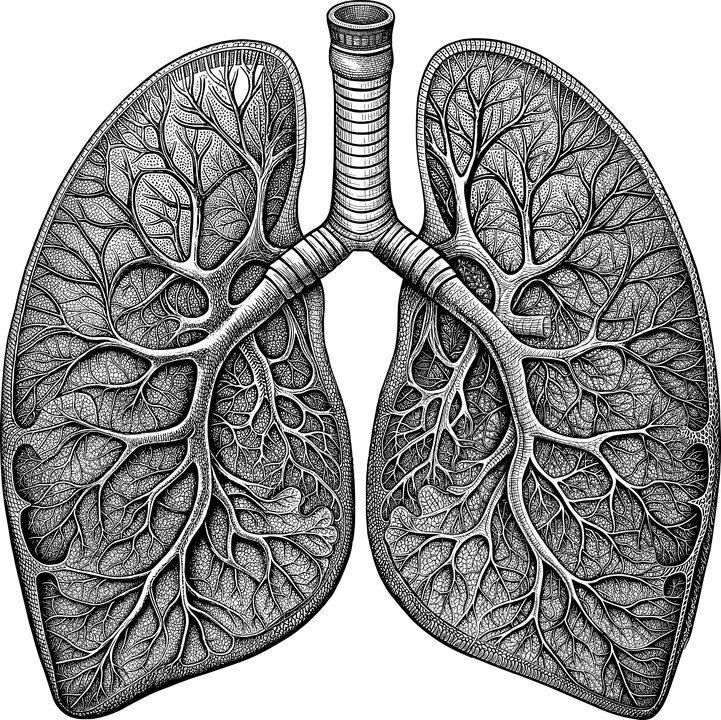

Les pathologies interstitielles sont des pathologies qui touchent le tissu connectif du poumon. L’un des exempte bien connu de pathologie interstitielle est par exemple la fibrose pulmonaire et toutes les pneumoconioses (silicose, asbestose, etc.)

Les pathologies interstitielles affectent le tissu conjonctif des poumons, comme la fibrose pulmonaire et les pneumoconioses (silicose, asbestose), qui peuvent endommager progressivement le tissu pulmonaire.